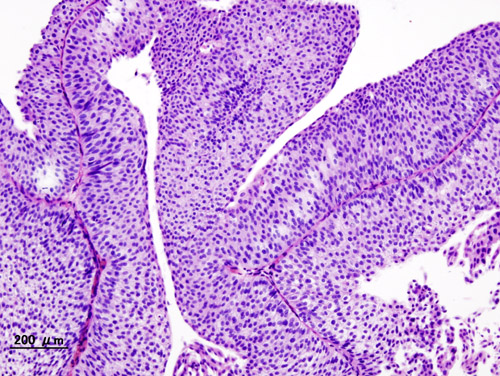

Bladder cancer is the sixth most commonly diagnosed cancer in the United States, according to the NCI. More than 90 percent of the 80,470 new cases of bladder cancer expected to be diagnosed in the United States in 2019 will be classed as urothelial carcinomas because they will arise in cells that comprise the transitional cell urothelium that lines the bladder.

Research, including a paper published in the AACR journal Clinical Cancer Research, has shown that up to 30 percent of urothelial carcinomas have an alteration in one of the four FGFR genes, with the most common alterations being mutations in the FGFR3 gene. These data suggest that targeting FGFRs might provide a new approach to treating urothelial carcinoma.